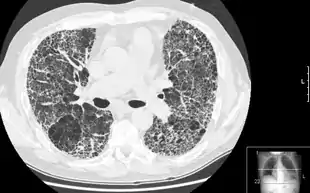

HRCT of lung showing extensive fibrosis possibly from usual interstitial pneumonitis. There is also a large emphysematous bulla.

The diagnosis can be confirmed by lung biopsy.[3] A videoscopic assisted thoracoscopic wedge biopsy (VATS) under general anesthesia may be necessary to obtain enough tissue to make an accurate diagnosis. This kind of biopsy involves placement of several tubes through the chest wall, one of which is used to cut off a piece of lung to send for evaluation. The removed tissue is examined histopathologically by microscopy to confirm the presence and pattern of fibrosis as well as presence of other features that may indicate a specific cause e.g. specific types of mineral dust or possible response to therapy e.g. a pattern of so-called non-specific interstitial fibrosis.[3]